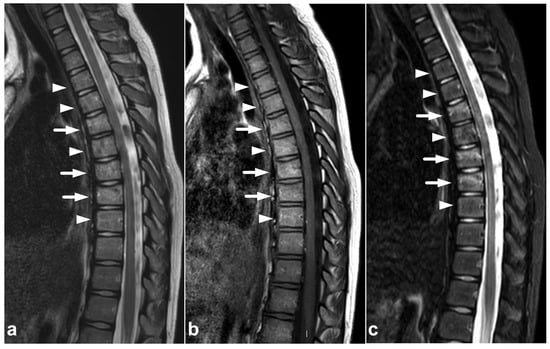

Figure 3.

(a) Sagittal T2-weighted. (b) Sagittal T1-weighted. (c) Sagittal left-sided off-midline T1-weighted. (d) Sagittal right-sided off-midline T1-weighted. (e) Sagittal left-sided off-midline T1-weighted. (f) Axial T2-weighted. (g) Axial T1-weighted. A 2-year-old female, motor vehicle accident. Chance-type fracture through the vertebral body and the posterior arch is seen in L2 (white arrows). L2/3 and L3/4 facet joints are widened and subluxated (black arrowheads). Kyphosis at level L2. Compression fracture in L3 (white asterisk) and contusion in L4 (black asterisk). Posteriorly, there is a longitudinal intradural hematoma (black arrows) and epidural hematoma (white arrowheads). A paraspinal hematoma (curved arrows) and posterior subcutaneous hematoma are also seen.

The use of MRI in acute spinal cord trauma was first described in 1983 [60,61] and it has been the gold standard in imaging these injuries ever since. T1-weighted, T2-weighted, and STIR sequences are the cornerstones in assessing the cord [49]. Diffusion-weighted imaging (DWI) and diffusion tensor imaging (DTI) might be useful in detecting subtle injuries and as a prognostic biomarker, but their role in clinical practice is not fully established yet [62,63,64,65,66]. Susceptibility-weighted imaging (SWI) or T2*-weighted sequences might increase the sensitivity in the case of small intramedullary hemorrhages but are technically challenging to obtain due to pulsation and motion artifacts [67,68]. Cases of spinal cord injuries are presented in Figure 15 and Figure 16.

Figure 15.

(a) Sagittal T2-weighted. (b) Sagittal T1-weighted. (c) Sagittal T2-weighted fast field echo. (d) Coronal STIR. (e) Axial T2-weighted, level of the lower end plate of C6 (caudal dotted line in the image (b)). (f) Axial T1-weighted, level of the lower end plate of C6 (caudal dotted line in the image (b)). (g) Axial T2-weighted, level of the lower end plate of C5 (cranial dotted line in the image (b)). (h) Axial T1-weighted, level of the lower end plate of C5 (cranial dotted line in the image (b)). A 17-year-old male after diving into shallow water. The spinal cord is edematous approximately from the level of the lower end plate of C4 to the lower end plate of C6 (black arrowheads). There is a hemorrhagic contusion in the right-sided grey matter (white arrows) and a contusion without macroscopic hemorrhage on the left side (white arrowheads). Hematoma can be seen in the anterior epidural space (curved arrows). There are fractures of vertebral bodies and posterior arches of C5 and C6 (asterisks and small arrows).

Figure 16.

(a) Sagittal T2-weighted. (b) Coronal STIR. (c) Axial T2-weighted (dotted line in the image (a)). A 2-year-old female, severe cervical fracture–dislocation after a car accident. The spinal cord is transected. The cord caudally to the transection site (arrows) is dislocated posteriorly and on the right side of the cranial end of the transected cord (arrowhead). An extensive hematoma is seen around the fracture.